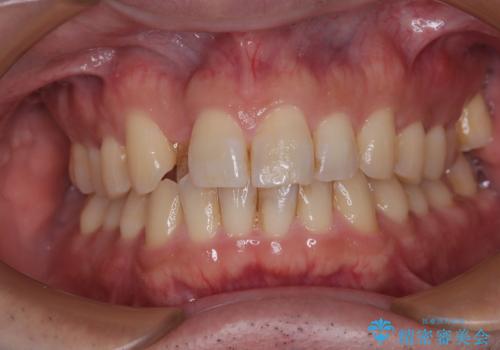

- 上下の八重歯を気にして来院された患者様です。

上下ともに八重歯の後ろの歯を1歯ずつ抜歯し、補助装置(リンガルアーチ)を用いて八重歯の位置を改善し、その後インビザラインにより矯正治療を行うこととしました。

途中海外留学をされたため、治療期間は長くなりましたが、事前に補助装置やワイヤー装置を併用したことで、きれいな歯列に仕上げることができました。